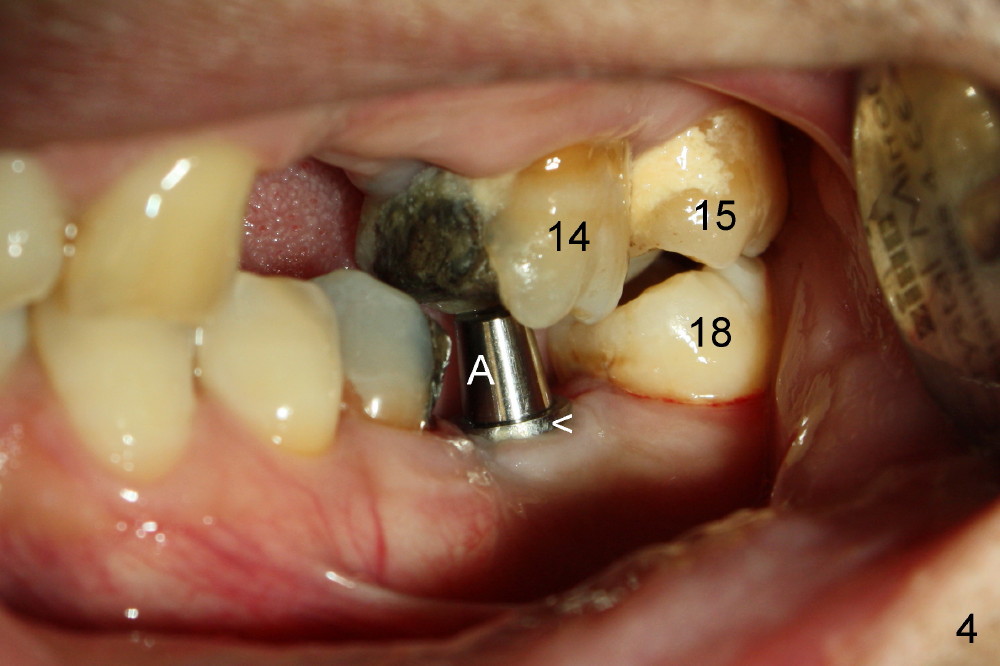

Mr. Zhou is in his fifties. Finally he starts implant restoration. But he has financial constraint. It appears that implant restoration at the site of #19 is the most rewarding in term of restoration of his mastication with a single implant (Fig.1). The implant is apparently placed at the proper level (Fig. 2: I, 6x17 mm). The implant is osteointegrated with minimal bone resorption at crest six months later (Fig.3). The teeth #15 and 18 cannot occlude when 4.5x5 mm abutment (Fig.4: A) is placed at #19 implant (<). It takes a while to trim the unipost from the top gradually in order to let #15 and 18 have normal occlusal contact (Fig.5 mirror image). By that time, the abutment is approximately 2.5 mm tall.